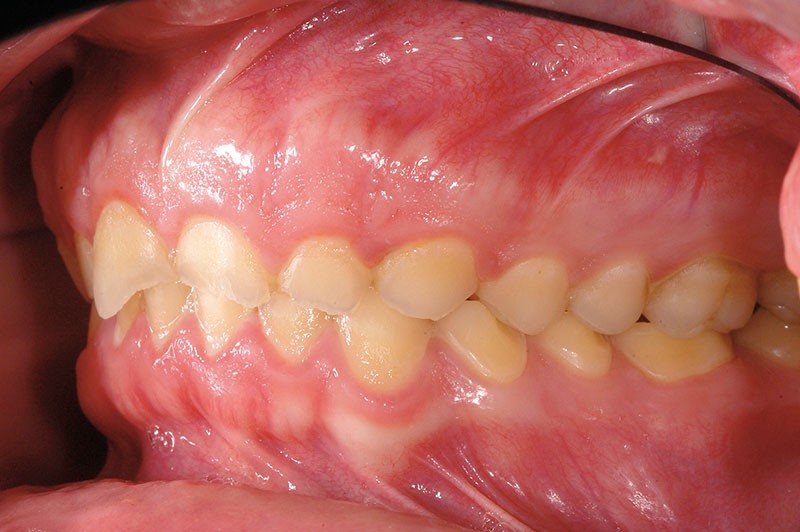

À l’examen clinique, les dents, principalement antérieures, présentent des pertes de substances importantes de classe V selon la classification ACE (Anterior Clinical Erosive Classification) de Vailati [1] (fig. 1 à 6).

Les examens complémentaires, dont un sondage parodontal, montrent l’absence de maladie parodontale (fig. 7).

Le parodonte marginal est de type 1 selon la classification de Maynard et Wilson [2]. On note également la présence d’une grande quantité de gencive attachée située apicalement par rapport aux lésions dentaires.